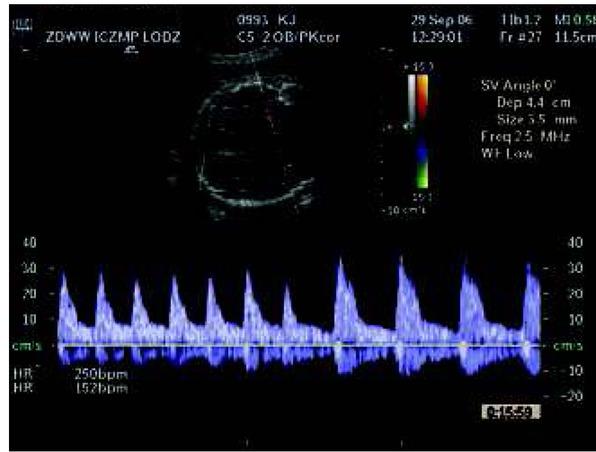

Isolated complete heart block in Doppler evaluation in a fetus with normal heart anatomy.Ryc. 6. Izolowany blok serca płodu (przy prawidłowej budowie serca) w badaniu za pomocą Dopplera.